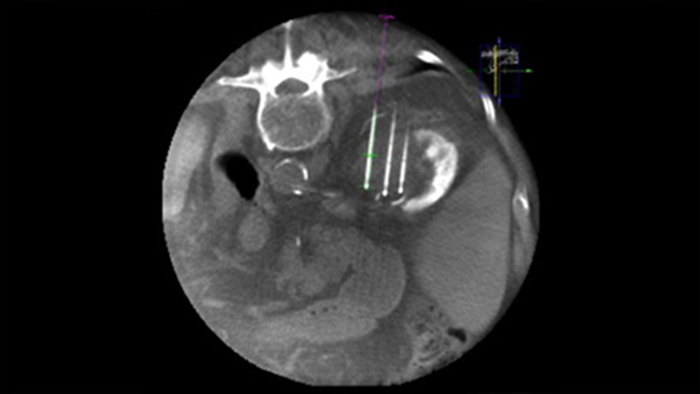

La ablación percutánea (radiofrecuencia, microondas y crioablación) es un tratamiento mínimamente invasivo de eficacia comprobada de tumores renales, hepáticos, pulmonares y óseos. Es fundamental definir los límites del tumor y decidir un número óptimo de agujas y la trayectoria de la aguja correspondiente para poder realizar un tratamiento tumoral completo y no causar daños en el tejido circundante. Navegar con precisión en dosis bajas hacia la lesión de interés sin necesidad de cambiar la posición de la aguja aumenta la oportunidad de éxito y reduce el riesgo de complicaciones en las biopsias o ablaciones. La confirmación del criterio de valoración del tratamiento de ablación se puede lograr con imágenes 3D mientras el paciente aún se encuentra en la mesa.

SmartCT Soft Tissue ofrece una técnica de adquisición de CT de haz cónico (CBCT) aumentada con guía paso a paso, visualización 3D avanzada y herramientas de medición; todas en el módulo de pantalla táctil de la mesa.